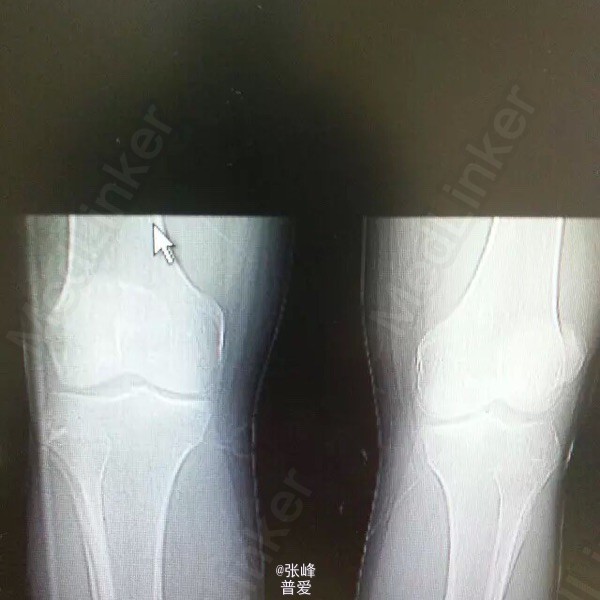

患者刘曙平,男,57岁。 左膝部肿痛、活动受限1天。 患者于昨天无明显诱因出现左膝肿胀,疼痛,伴活动受限。自行服药及局部外敷药治疗(具体不详),效果不明显,疼痛渐加重。为求进一步诊治,就诊我院,门诊了解病史、查体后以“左膝滑膜炎”收入院。 起病以来,精神一般,未进饮食,二便未解,体力尚好。 既往史:发现“高血压”4年,规律服用“倍他乐克”“波依定”,血压控制可;发现“痛风”20余年,目前症状控制一般。否认糖尿病、肝炎、结核等病史,否认药敏史。

体格检查:T:36.5℃ P:74bpm R:18bpm Bp:138/80mmHg。神志清晰,精神可。胸廓无压痛,双肺叩诊呈清音,听诊呼吸音清晰。心率74bpm,律齐,各瓣膜听诊区未闻及病理性心杂音。腹平,软,无压痛及反跳痛,肝脾肋下未触及,肠鸣音3-5次/分。 专科情况:左膝明显肿胀,膝眼饱满,局部皮温稍高,局部压痛,活动受限,背伸尚可,屈曲90度后受限,左足背动脉搏动良好,左足趾活动可。

诊断:左膝滑膜炎 诊疗计划:1.完善相关检查,如血尿常规分析、肝肾功能等。 2.对症治疗,观察左膝情况。 3.请示上级医师指导治疗。 者诉左膝部疼痛不适,无诉其他特殊不适,大小便正常。赵晶晶主治医师查房:患者根据既往病史、查体检查,目前考虑诊断左膝关节痛风性关节炎可能性大,暂以抗尿酸、对症支持及局部理疗,